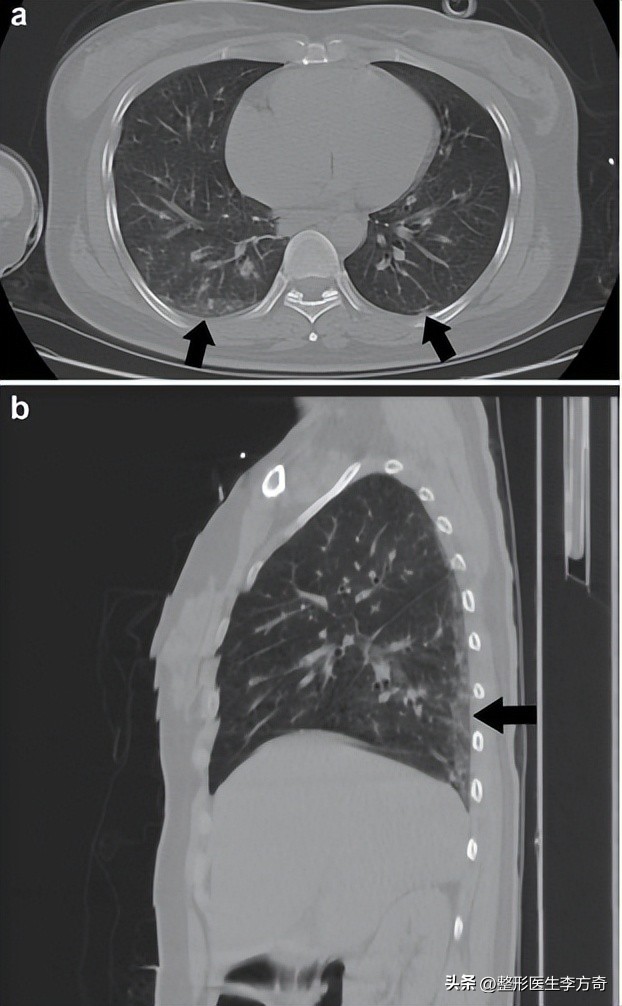

在本次案例的情况中,根据组织病理学检查,在两个肺的间质性肺的小血管腔中有无定形嗜碱性物质的广泛栓塞,并且在阴道壁中有相同物质的大量积聚,最后得出结论,认为本例肺栓塞是由玻尿酸引起的。